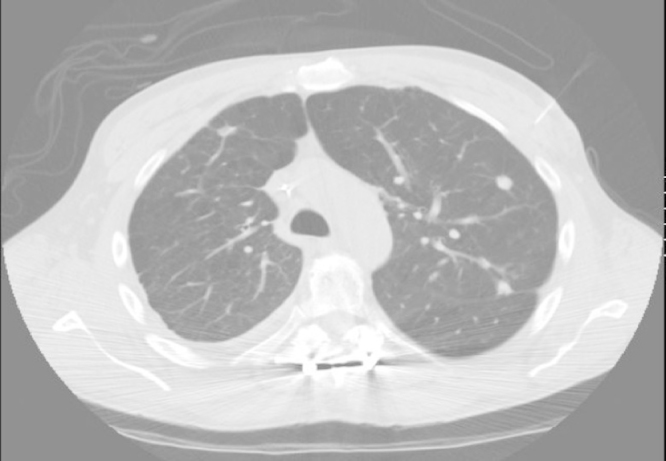

The human body is an unsuitable environment for heartworm and as the nematode dies it embolizes the pulmonary vessels causing infarction and eventual nodule formation that can present as a solitary or multiple pulmonary nodules …